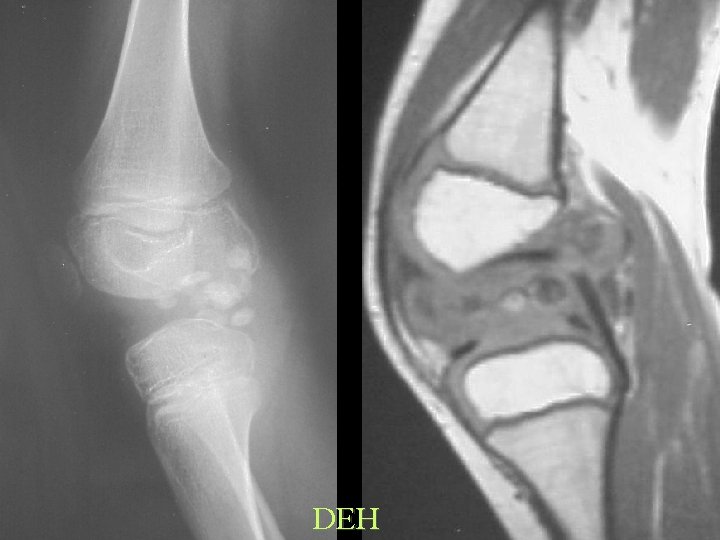

DEH

Exclude OSSIFICATION

Ossification Look for: • Trabeculation • Cortico-medullary differentiation • Fat on T 1